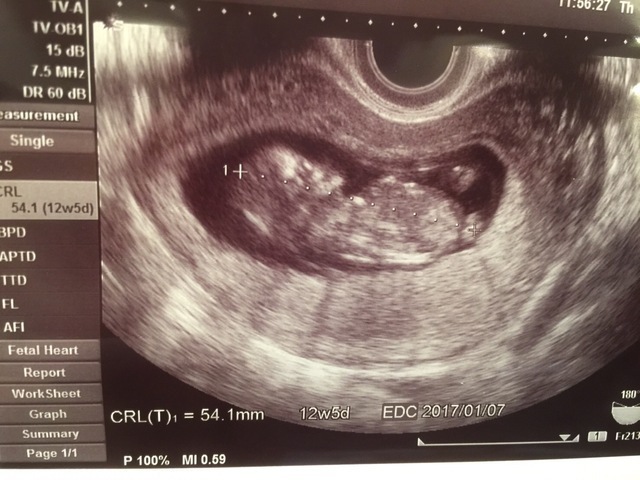

12週5日(12w5d・男の子)|うさがわ さん(36歳)

エコー写真撮影時のエピソード:

初めて顔がしっかりわかるエコー写真がもらえて、実感が出てきました!少しずつ人間ぽくなってきてエコーを見るのが楽しみになってきました。

この写真を見て旦那さんがとても喜んでいたのが忘れられません。不安もたくさんありましたが、先生が優しく丁寧に話してくれたので安心できました。